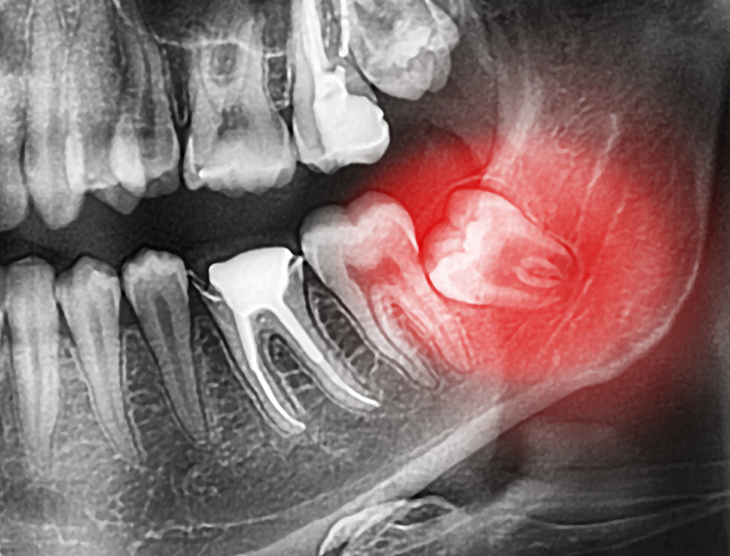

Irrespective of the cause, Dr. Davidson and her team prioritize ensuring both you and your child feel at ease with the treatment plan. Utilizing local anesthetic, Dr. Davidson will extract your child's tooth. If the tooth is impacted or the extraction proves complex, Dr. Davidson will discuss sedation options with you.